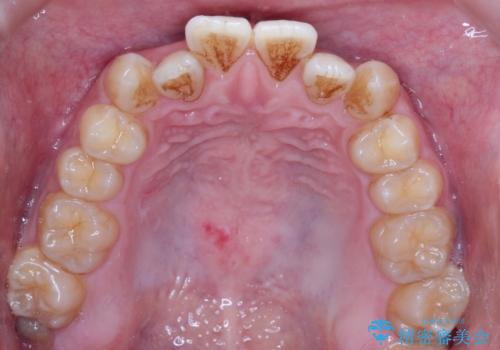

前歯のデコボコ インビザラインによる目立たない矯正

- 前歯のデコボコを主訴に来院された患者様です。

目立たないそうちをご希望されたので、インビザラインにて治療することとしました。

歯と歯の間をわずかに削ってスペースをつくり、デコボコを改善しました。